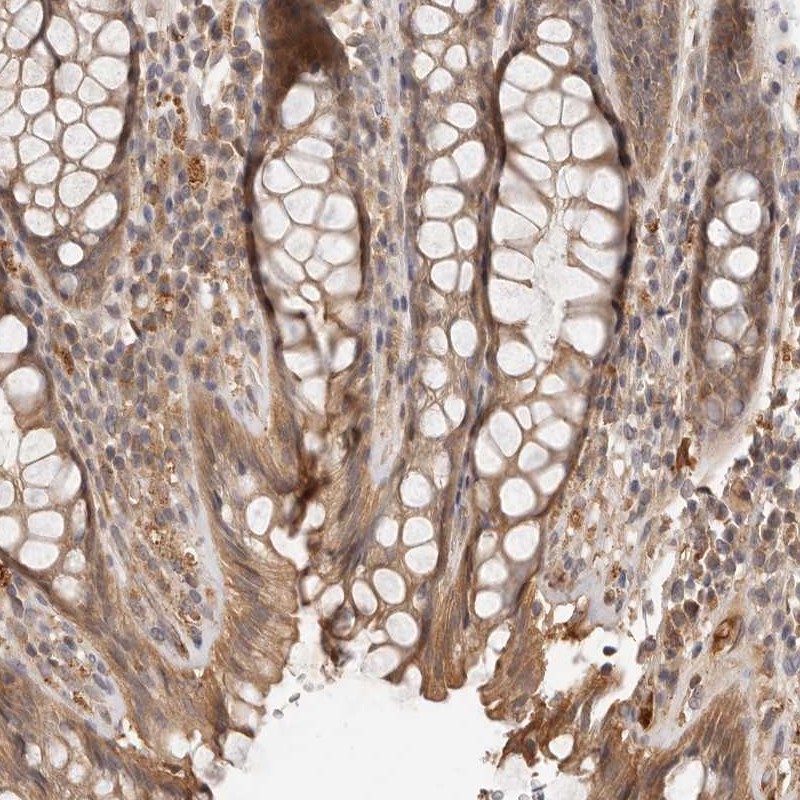

Immunohistochemical staining of human rectum shows moderate cytoplasmic positivity in glandular cells.